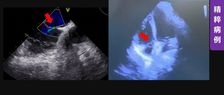

近日,四川省人民医院心脏超声与计算心脏病学团队、结构性心脏病团队于《Quantitative Imaging in Medicine and Surgery》分享的病例,通过多模态超声精准识别舒张期二尖瓣与三尖瓣反流,并成功通过希氏束起搏实现血流动力学逆转,为临床提供了宝贵的诊断与治疗思路。